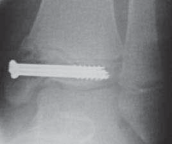

TILLAUX FRACTURES: SALTER-HARRIS TYPE III FRACTURES

1. An anterolateral approach to the ankle is used.

2. This fracture can be fixed by a distal-to-proximal, and anterior-to-posterior, compressive interfragmentary cancellous screw (

TECH FIG 3

).

3. Again, cannulated screw fixation may be used if the surgeon prefers it to the use of noncannulated screws.

22. Crossing the physis is not contraindicated in this fracture pattern because by definition the medial physis is closed and complete physeal closure is imminent.

---

A B C D

TECH FIG 3•

Tillaux fracture treatment.

A,B.

Tillaux fractures are often not seen clearly on plain radiographic views, and it is important to obtain a mortise view to see the fracture fragment that is obstructed by the fibula in standard AP views.

C,D.

CT scans often aid in fracture characterization and operative planning.

E,F.

These fractures are fixed with compressive interfragmentary cancellous screws across the fracture site, without concern for transphyseal fixation as these patients are always

E F close to skeletal maturity.